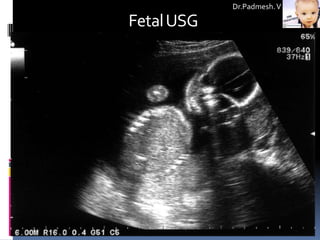

1. Fetal Visualization:

a) USG:

 Noninvasive procedure for imaging fetal anatomy.

 Harmless to both the fetus and the mother.

 Anatomical lesions, including some

genitourinary, gastrointestinal, skeletal, and central nervous system

abnormalities and congenital cardiopathies, can be visualized by

ultrasound between 16-20 weeks' gestation.

 Ultrasound also is used to guide invasive sampling, such as

amniocentesis, CVS, cordocentesis, and various fetal biopsies.

Fetal USG